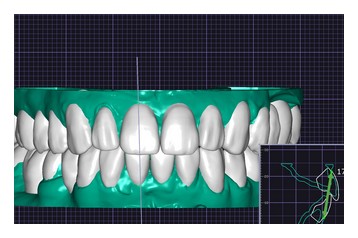

На этапе планирования комплексной реабилитации, было проведено интраоральное сканирование, фотопротокол, цифровая аксиография, данные которой использовались для последующей настройки виртуального артикулятора. Определено соотношение челюстей по нейромышечному протоколу с применением Миомонитора J5(TENS). По показаниям проведена репозиция нижней челюсти, в связи с чем была изготовлена каппа, фиксирующая терапевтическое исходное положение, так называемое Therapeutic Reference Position. То есть планирование имплантации проводилось уже не в исходном патологическом положении нижней челюсти, а в определенном терапевтическом, обеспечивая наиболее функционально выгодное расположение имплантатов относительно костного гребня. Позиционирование имплантатов на уровне 2.5, 2.6, 3.6, 4.6 - проводились под контролем хирургического шаблона.По завершению этапа остеоинтеграции и санации полости рта, приступили к этапу ортопедического лечения. В работе учитывались пожелания пациентки по эстетике. Объединив все полученные данные, мы приступили к построению зубных рядов с применением цифровых протоколов. В Программе Exocad был произведен расчет по индексу Шимбачи (LVI) ,что позволило определиться с оптимальной длиной фронтальной группы зубов, проведена моделировка Wax-up (Рис.8-9).

Рис. 9 Рис. 9